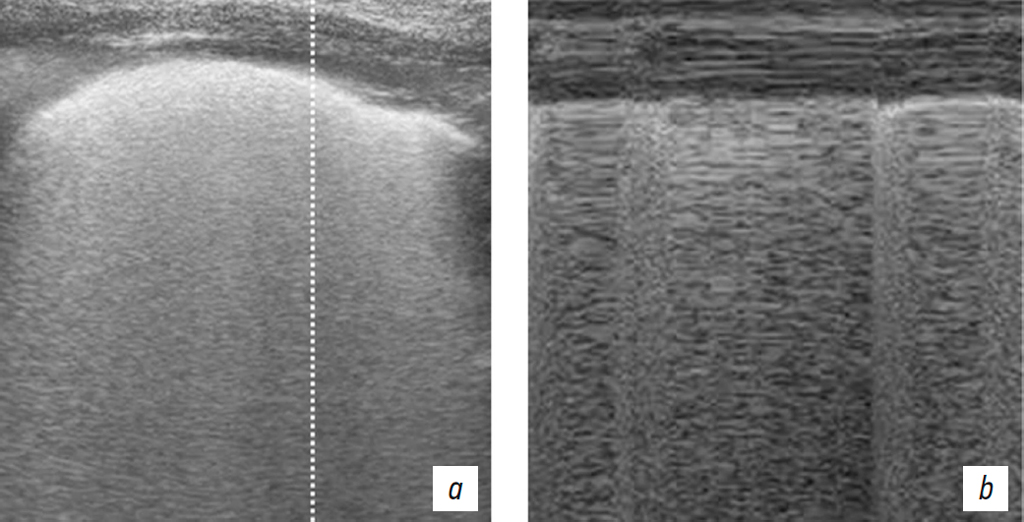

Furthermore, unilateral coexistence of pneumothorax and EPS emphysema was observed in five patients (Fig. 6). In three of these patients, the drainage tube was positioned in the EPS, which resulted in failure to drain the pleural cavity, progressive clinical deterioration, and the development of subcutaneous emphysema (Fig. 7). In one case, severe EPS emphysema was associated with respiratory failure (Fig. 8). US revealed findings characteristic of pneumothorax, including the absence of pleural sliding (Fig. 9).

Fig. 9. Patient A. Ultrasound of the pleural cavity (BLUE protocol): a, B-mode; b, M-mode. Extrapleural emphysema in the left hemithorax.

Рис. 9. Пациент А. УЗИ плевральной полости протокол «Blue»: а — B-режим; b — М-режим. Эмфизема ЭПП левого гемиторакса.